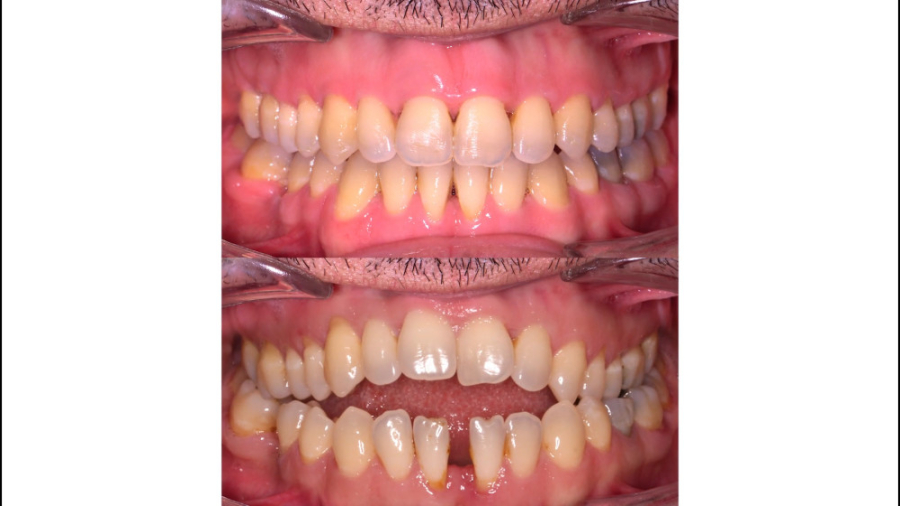

قبل و بعد از ارتودنسی مراجعین کلینیک مدرن ونک(۰۹۱۲۰۰۴۵۸۷۶)

5280 بازدید